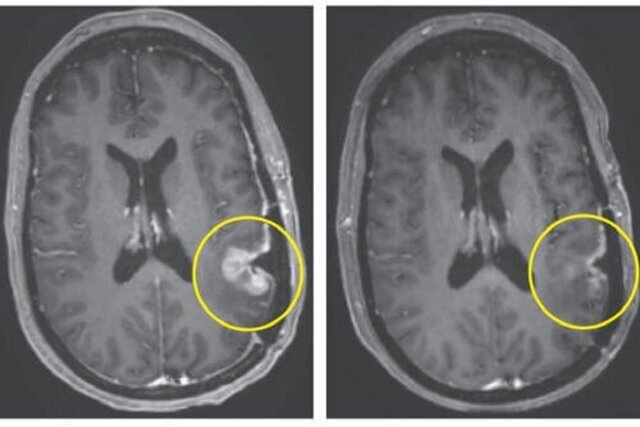

قابل توجه است که تنها چند روز پس از درمان، بیماران شاهد کاهش قابل توجهی در تومورهای خود بودند، به طوری که یک بیمار در عرض پنج روز به پیشرفت تقریباً کامل تومور دست یافت.

یکی از بیماران، مردی ۷۲ ساله بود که شاهد کاهش بیش از ۶۰ درصدی تومور خود بود که به مدت شش ماه ادامه داشت، در حالی که یک زن ۵۷ ساله تنها پنج روز پس از یک تزریق، تقریباً پیشرفت کامل تومور داشت.